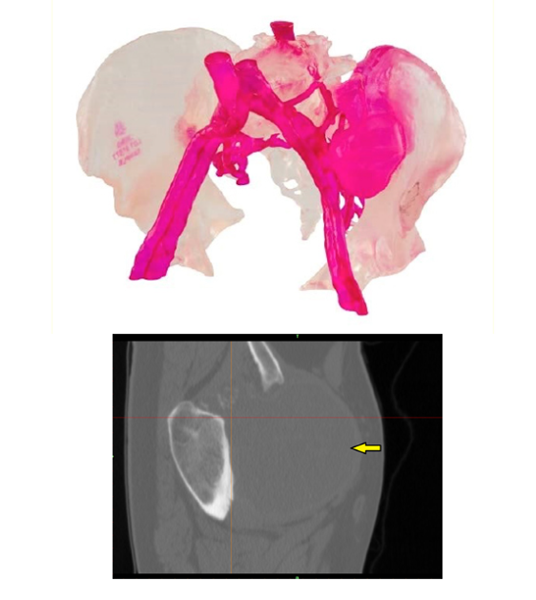

△使用3D打印假體修復(fù)因癌癥而受損的骨盆

Onkos Surgical是一家快速發(fā)展的肌肉骨骼腫瘤學(xué),和復(fù)雜骨科手術(shù)解決方案的領(lǐng)先創(chuàng)新者,My3D個性化骨盆重建系統(tǒng),是同類解決方案中的第一包括3D打印植入物、器械和模型,以及用于治療畸形、創(chuàng)傷、疾病和其他治療的綜合平臺,或可用于解決手術(shù)失敗重塑的高級規(guī)劃服務(wù)。

產(chǎn)品中包括針對患者的植入物,以及用于髖臼重建和跨越骨盆多個區(qū)域的高級重建。植入物的設(shè)計和打印具有獨特的功能,有助于解決骨骼和軟組織附著,以及解剖修復(fù)準(zhǔn)確性的挑戰(zhàn)。本次獲得的PFA批準(zhǔn),將再一次擴大該公司關(guān)于腫瘤學(xué),和復(fù)雜骨科解決方案的產(chǎn)品組合。